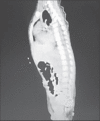

Figure 1

Computed tomography of the thorax (coronal section) suggesting bilateral posterior diaphragmatic defects with herniation of the liver on the right side and stomach, spleen and bowel on the left side